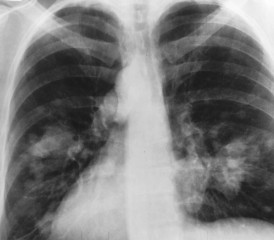

Lighter and hazy areas on the X-ray show possible mesothelioma tumors.

On a chest X-ray, pleural or pericardial mesothelioma tumors appear as wispy white areas around the lungs, while calcified tumors appear bright white. Bones appear white and healthy lungs are dark. Most abnormalities appear as lighter areas that are hazy or solid.

Large fluid buildup called pleural effusions, a common mesothelioma symptom, can make an entire lung field look “cloudy” or even completely white on an X-ray. Tumors and scarring may distort chest anatomy. Compressed lungs or a raised diaphragm can be visible on an X-ray.

X-rays are 2D, making it hard to determine if a tumor is in the lung, pleura or the mediastinum around the heart. Additionally, X-rays don’t clearly show peritoneal or testicular mesothelioma. CT, MRI and PET/CT scans offer more detailed images for all mesothelioma types.